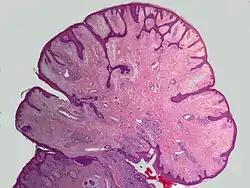

وَرَم وِعائي لِيفيّ[1][2] أو وَرَم لِيفي وِعائي[2] أو لِيفُوم وِعائِي[2][1] (بالإنجليزية: Angiofibroma) هيَ حطاطات صَغيرة ملساء لامعة، بُنية مُحمرة اللون أو لحمية اللون، طولها من 0.1 حتى 0.3 سم، تُوجد على جانبي الأنف وفي الجزء الأوسط من الوجنتين.[3] يحتوي هذا الورم على نسيج ليفي.